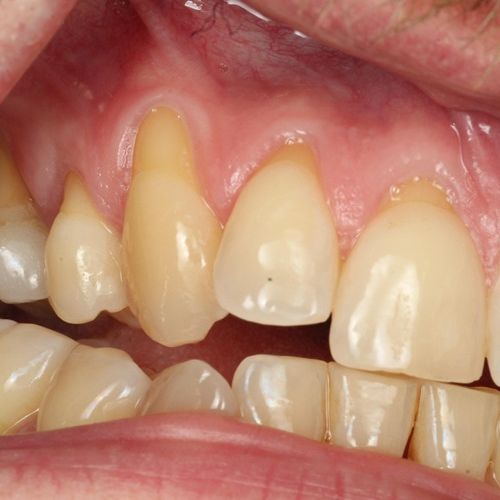

| Untreated severe gum disease | Gum disease treated and stabilised by Dr Halai |